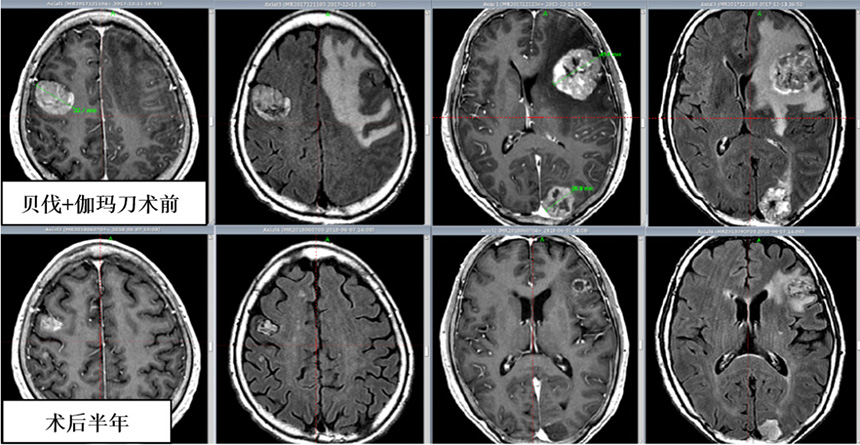

2、伽玛刀联合贝伐珠单抗治疗多发巨大脑转移瘤。经5年使用观察,该方法在提高病灶局控率、延长患者生存期的同时快速、显著降低了神经功能的损害,提高患者生存质量,为多发巨大脑转移瘤临床治疗的新思路。2019年神经外科分会肿瘤学组会议上我们分享此经验。